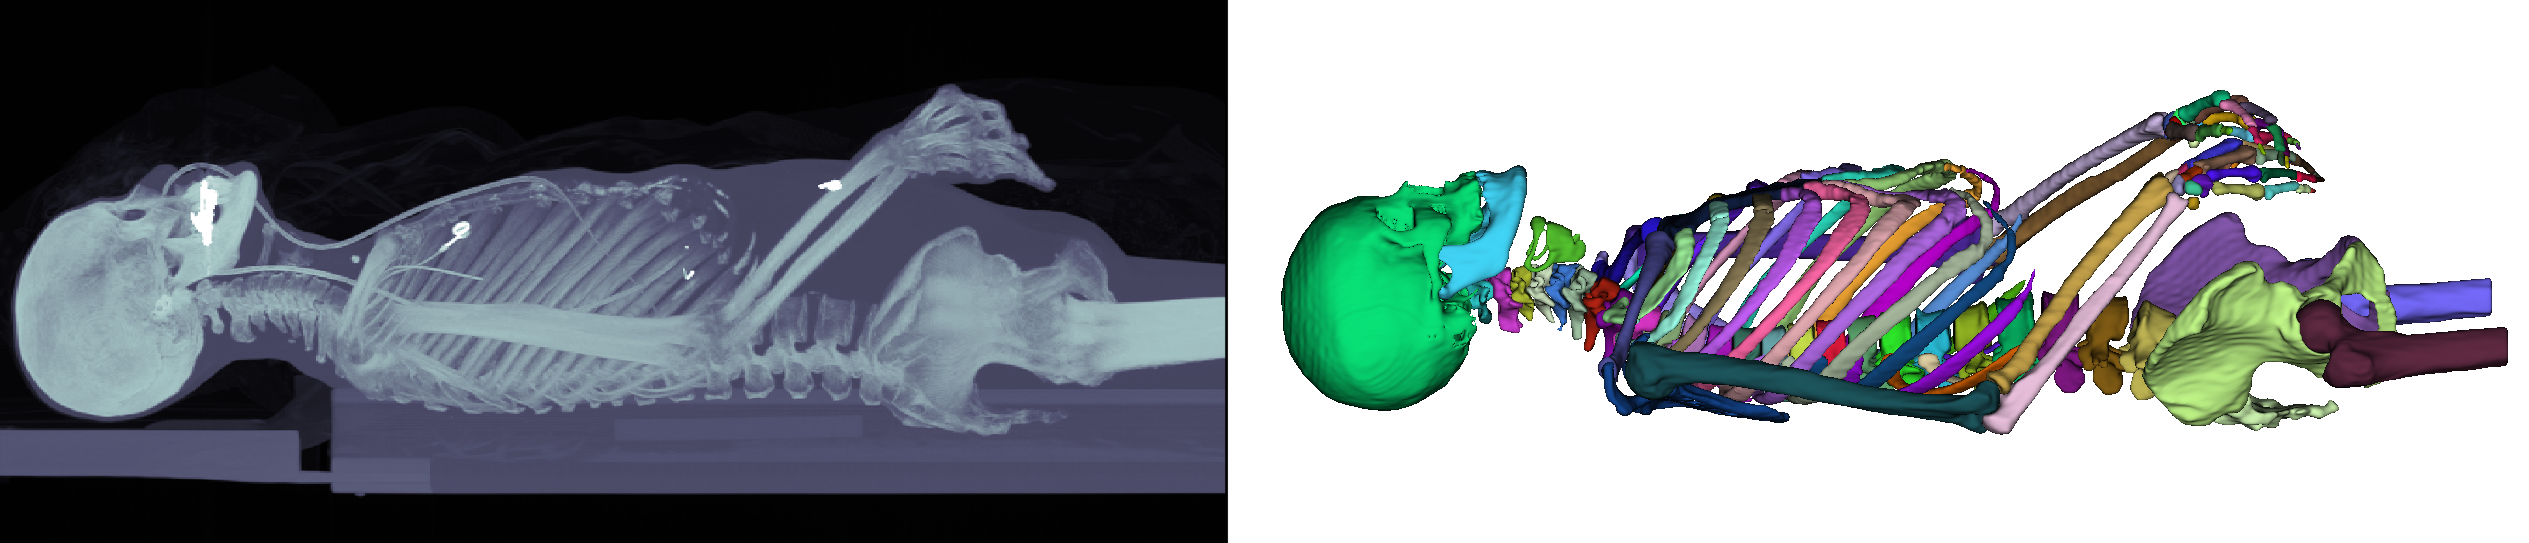

Refer to caption

Figure 1: Left: Maximum intensity projection of one of our upper body CT-scans. Right: The manual target segmentation depicting 125 different bones with individual colours.

In this work, we present, which kinds of preprocessing, network choice, loss function and data augmentation schemes are suitable for 3D medical image segmentation with many labels at once, using the example of distinct bone segmentation in upper bodies. Our contributions are: 1) We discuss essential adaptions concerning network choice and data augmentation when performing 3D segmentation in a many-label setting. 2) We examine different sampling strategies and loss functions to mitigate the class imbalance. 3) We present results on a 3D segmentation task with over 100 classes, as depicted in Fig. 1.